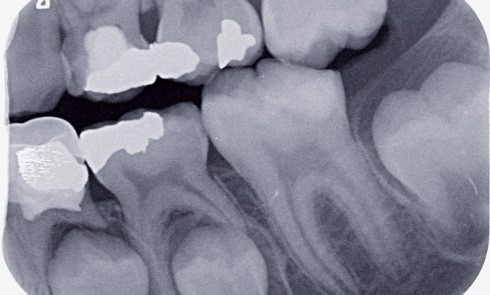

1. Quelle est votre première orientation diagnostique ?a) Odontomeb) Torus mandibulairec) Lithiase salivaired) Canine inclusee) Aucune des réponses La patiente ne...